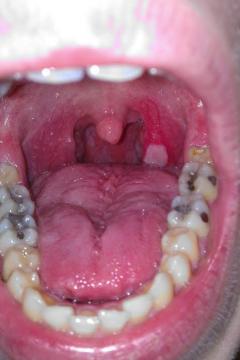

Pro větší náhled klikněte na obrázek

Biele fľaky v hrdle Michal92 - 6.7.2014 14:09:53

Dobrý deň, prekonal som rozsiahlu infekciu hrdla, dosť ma bolela ľavá strana hrdla na ktorom sa mi vytvoril biely hnisavý fľak, a opuchli mi mandle na tejto strane Momentálne beriem antibiotik 10ty deň, mandľa odpuchla, aj bolesť hrdla sa stratila no ten fľak na hrdle stále mam. Antibiotika ešte na 5 dni mám, 2x denne kloktam šalviový čaj. Viete mi prosím poradiť čo by ešte prispelo k rýchlejšiemu vyliečeniu hrdla ? Ďakujem

Odpověď zdravotníka na dotaz: Biele fľaky v hrdle

Dobrý den, omlouvám se za zpožděnou odpověď, nejdůležitější je, že klinicky se cítíte lépe. Zopakovala bych stěr z krku, mezitím pokračovala v antibiotikách a kloktání.